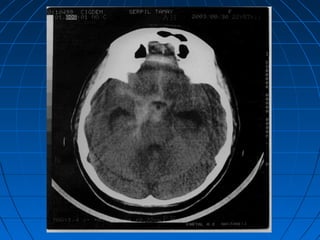

MASİF SPONTAN SAK + ICH + İVH + SDH…MASİF SPONTAN SAK + ICH + İVH + SDH…

MASİF SPONTAN SAK + ICH + İVH +…MASİF SPONTAN SAK + ICH + İVH +…

• 58 yaşında bayan hasta58 yaşında bayan hasta

• Ani bilinç kaybı şikayetiyle acilAni bilinç kaybı şikayetiyle acil

polikliniğe getirildipolikliniğe getirildi

• İlk NM:İlk NM: Bilinç kapalı; GKS: 5Bilinç kapalı; GKS: 5

Pupillalar anizokorikPupillalar anizokorik

YBÜYBÜ

5. günde exitus5. günde exitus